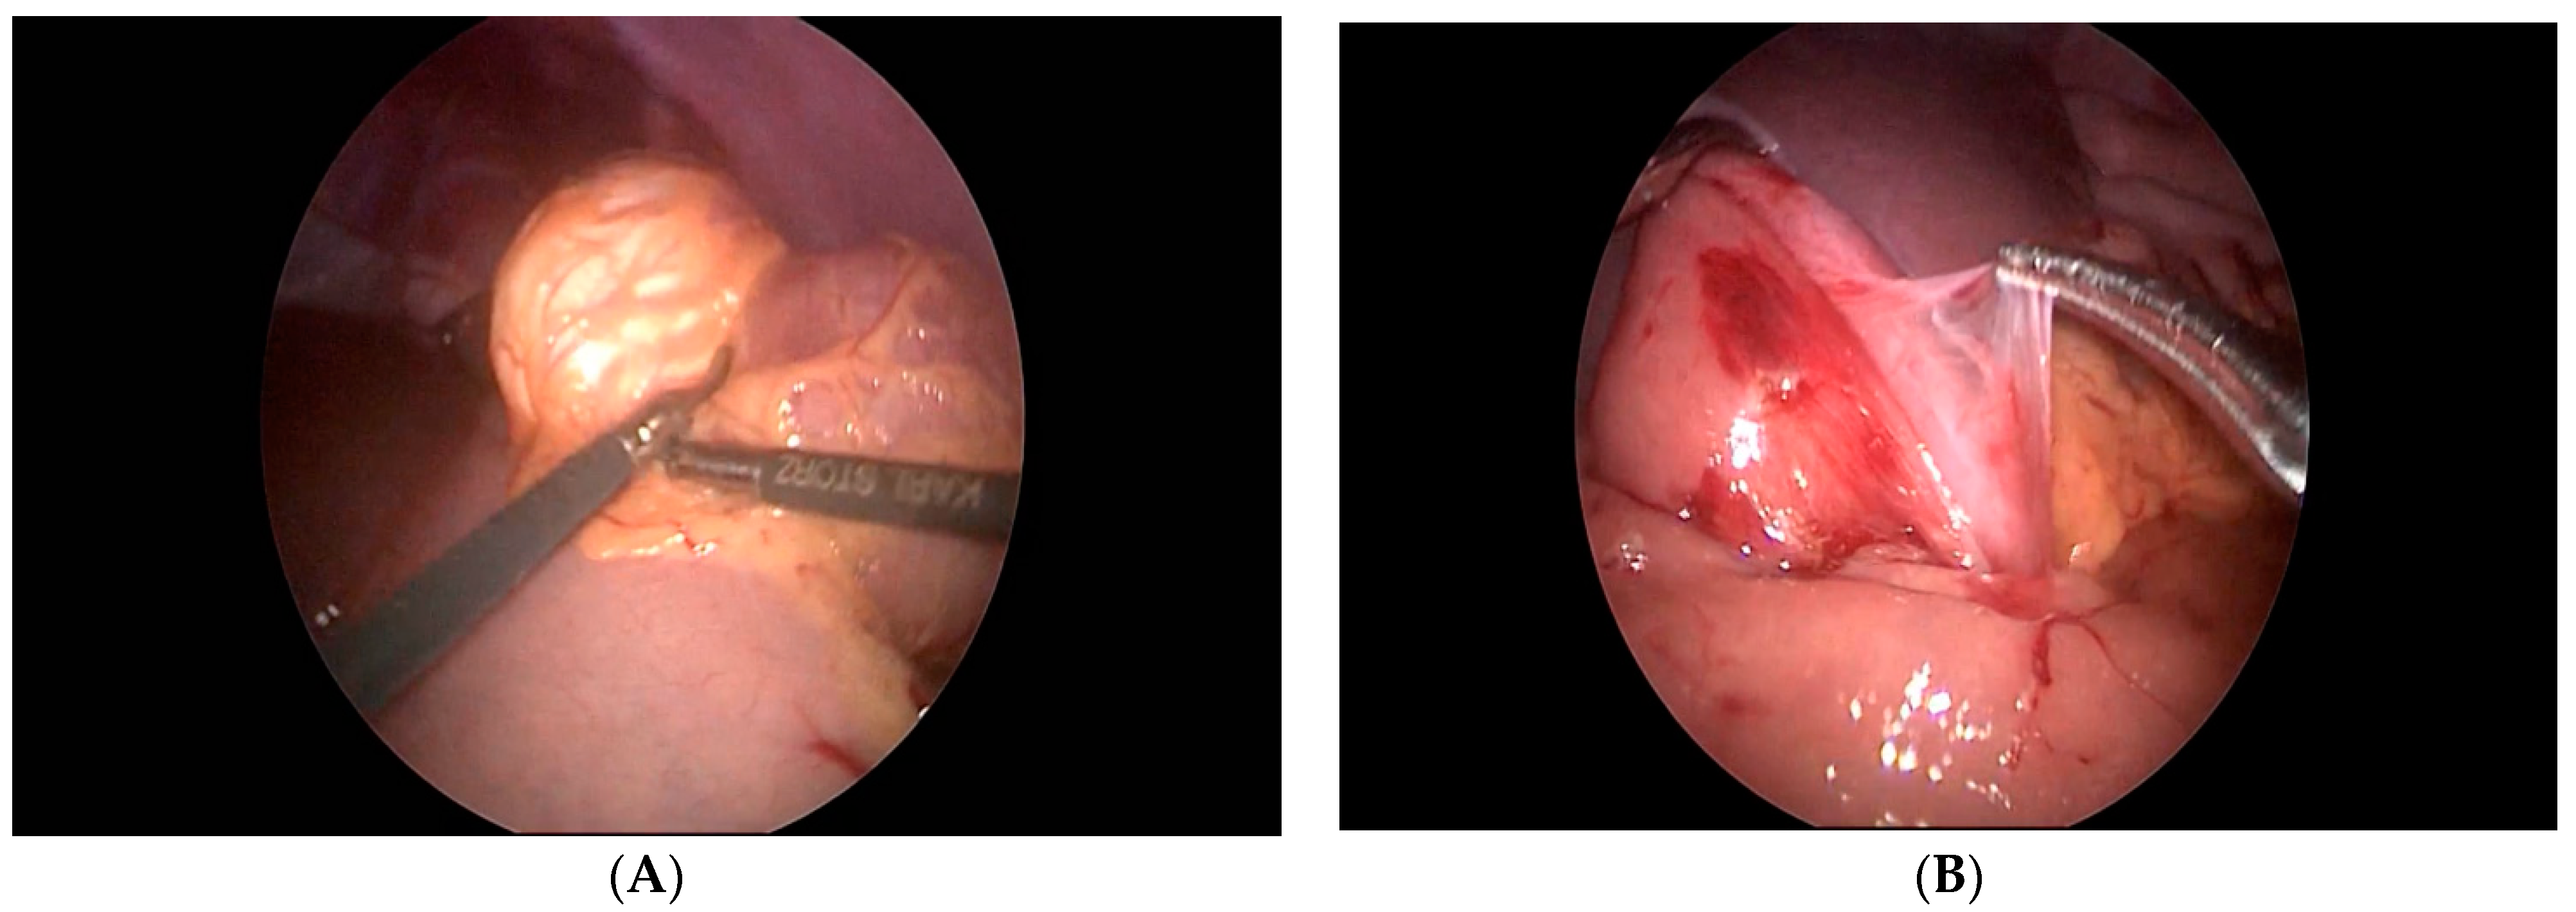

The seventh case in our case series is a 6-year-old boy who was referred to our clinic for a suspected ileocecal invagination. A hydrostatic desinvagination guided by ultrasound was attempted, and a patent ileocecal valve was confirmed. A pseudo kidney formation remained, indicating the possibility of an invagination of the duodenum and small intestine. A repeated ultrasound demonstrated that a pseudo-invagination was still present in the upper left quadrant. An MR-enterography was performed and demonstrated a 20-centimeter long suspected intussusception in the left hemiabdomen beginning in the third part of the duodenum and continued below the ligament of Treitz. Multiple polyps of the duodenum and jejunum were suggestive of Peutz–Jeghers syndrome as well. The most proximal polyp with a diameter of 6 cm produced a marked narrowing of the distal part of the duodenum and proximal jejunum. An esophago-gastro-duodenoscopy was performed, and a biopsy was taken. The biopsy confirmed the presence of a hyperplastic polyp of the duodenum. Then, the duodenum and jejunum were exposed using a combined laparoscopic–endoscopic “rendezvous” procedure (Figure 3A). A vertical incision was made on the highest position of the jejunal wall, and the mucosa was mobilized. However, the polyp could not be visualized during the first attempt. Then, we decided to use a partial Cattell–Braasch maneuver and resection of the ligament of Treitz for better mobilization of the duodenal mucosa (Figure 3B). After the resection of the ligament, the natural curvature of the duodeno-jejunal flexure was straightened. The straightened duodeno-jejunal junction allowed for the visualization and resection of the duodenal polyp (Figure 4). A second enterotomy was performed distally on the jejunum as well and two more polyps were resected (diameter 20 and 15 mm, respectively). The histology confirmed Peutz–Jeghers syndrome.

Figure 3.

(A) Endoscopic navigation by transillumination of the duodenum and jejunum, (B) Cattell–Braasch maneuver.

For decades after minimally invasive laparoscopic surgery has been introduced, duodenal lesions were impossible to resect using this approach. Recently, more and more surgeons are attempting to extend their field of work to the duodenum and endoscopic guidance can be of tremendous help during this procedure. Here, we reported a case of a duodenal polyp treated in this way. The Cattell–Braasch maneuver and resection of the ligament of Treitz were used in order to straighten the natural duodeno-jejunal flexure. In 1960, Cattel and Braasch described the technique for the mobilization of the third and fourth portion of the duodenum that is used until today [16]. This maneuver consists of dissection of the line of Toldt from the common bile duct until the ligament of Treitz. Additional mobilization of the suspensory muscle of the duodenum (ligament of Treitz) was performed in the case we report here for complete mobilization of the duodenum. After the resection of the ligament, the natural curvature of the duodeno-jejunal flexure was straightened. The straightened duodeno-jejunal junction allowed for the visualization and resection of the duodenal polyp during repeated mucosal mobilization. Nowadays, laparoscopic endoscopic cooperative surgery, combining endoscopic submucosal dissection and laparoscopic seromuscular incision, is reported to be successful in treating duodenal lesions as well [17].